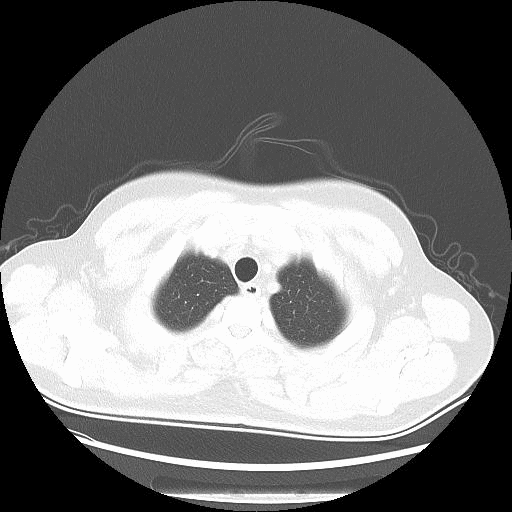

入本院第19天CT.gif